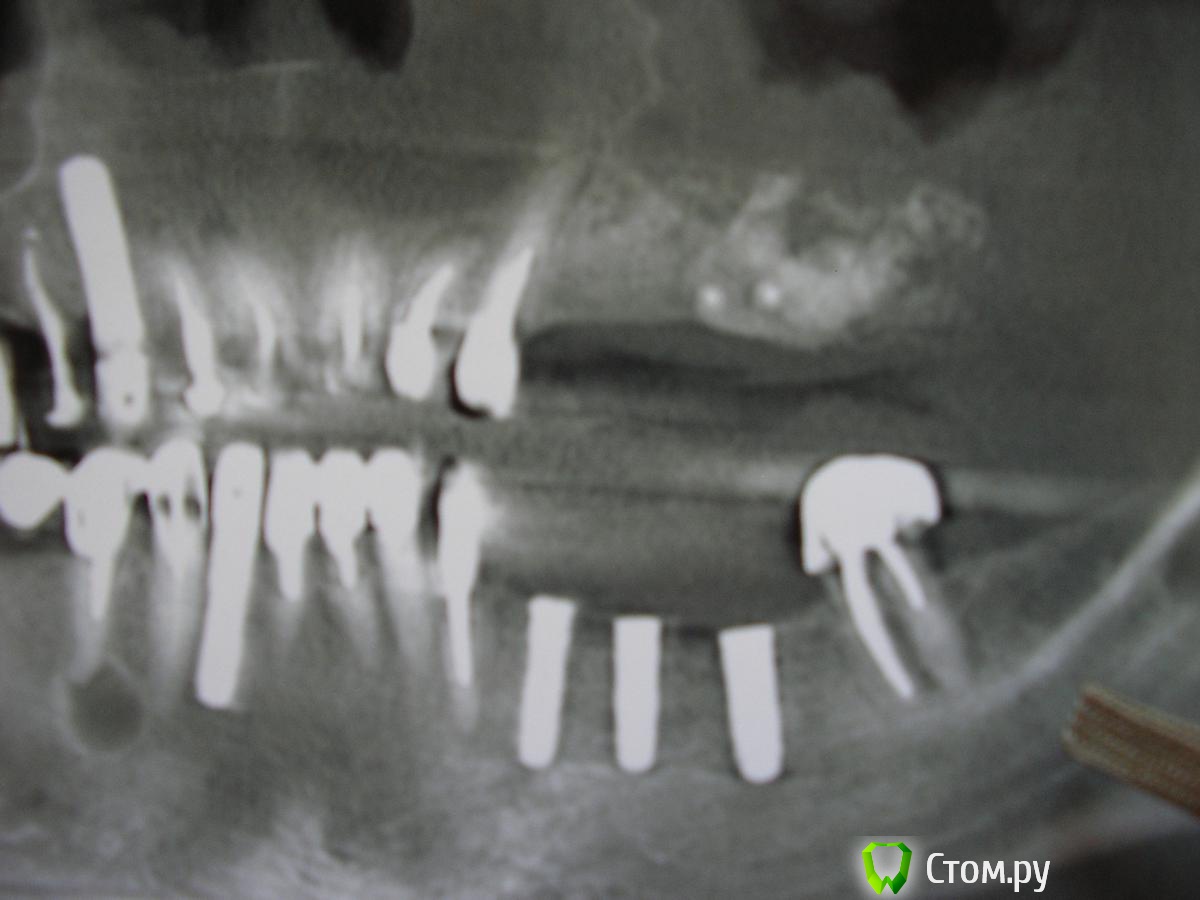

Alvina Опубликовано 25 июля, 2014 Поделиться Опубликовано 25 июля, 2014 4 месяца назад я сдела открытый синус-лифтинг (прошел успешно), а два дня назад в эту область мне док поставил импланты 24;25;26;27. Предварительно мы с ним обсуждали сколько ставить имплантов 3 или 4 и он посоветовал 4 - сказал что это более надежно (типа могут простоять всю жизнь) и плюс к этому удобно протезировать разбив на две группы : 24 - 25 и 26-27. Я согласилась. После установки сразу сделали КТ - результат на фото. Импланты 24 и 25 стоят очень близко. Поэтому очень хочу посоветоваться как будет правильно (оптимально) поступить в моем случае? Судя по всему возможны 3 варианта:1). Оставить все как есть.2). Удалить имплант 25 и запротезироваться на оставшихся трех.3). Удалить 24, подождать какое-то время и вновь поставить этот имплант в более правильную позицию. Ну и какой из этих вариантов лучше? 1 Ссылка на комментарий

Alvina Опубликовано 26 июля, 2014 Автор Поделиться Опубликовано 26 июля, 2014 Я, кажется, понимаю о чем идет речь - о темных "обводах" на трех имплантах нижней челюсти, правильно? Там изначально была очень непростая ситуация - ширина костного гребня порядка 2, 5 мм при приемлемой высоте. Док мне делал костную пластику с установкой нерезорбируемой мембраны - ее пришлось удалить через 4 месяца (оголился ее уголок). При удалении док увидел, что кость уже сформировалась и все хорошо отвердело, поэтому месяц назад мы решили поставить 3 нижних импланта. Интересная деталь - в момент установки он попробовал вкрутить имплант сверлом и ...кость не поддалась стандартному усилию, имплант не пошел. Док сказал, что убывает (вот здесь за точность терминологии не ручаюсь - во время операции я все же волновалась и могла немножко перепутать), что при отсутствии зубов в первую очередь убывает губчатая кость, которая в середине гребня и кортикальные пластины почти слипаются, поэтому сейчас он ставит импланты частично в кориткальные пластины, а они очень твердые. Поэтому док решил медленно мне вкрутить импланты вручную, что и сделал...И в первое время после операции все было нормально (как обычно при имплантации - она у меня уже не первая), но спустя 12 дней вдруг напухла десна со стороны языка, покраснела, образовалось какое-то вздутие (но не нагноение - все было твердым, не булькало), которое сильно разболелось...Док сделал КТ (оно на фото) и сказал, что это, скорее всего, реакция надкостницы, прописал курс антибиотиков по новой...Через 3 дня все начало проходить и сейчас с низу уже нет ни покраснения, ни набухания, ни болезненности...И я уже думала, что пронесло...Только вот после ваших комментариев задумалась...Я не знаю видно ли это вам, но я, смотря на оригиналы КТ, четко вижу что если сравнить 2 КТ (с интервалом в две недели) от 9 июля (она выложена в этом посте) и от 23 июля (она выложена в первом посте) черные обводы у корней имплантов увеличились, а болезненность и пр., наоборот, прошла...Вот такая загогулина...с хорошей десной, может большинство имплантатов и удастся спасти, если без радикализма.. и если там нет апико на верхушках имплантов, судя по контрастности, но тут понаблюдать, если даже перегрев, а не перерасширение, кость может и стрепеть И вот я не знаю, может кость уже стерпела? Десны у меня, кстати, хорошие - толстые, плотные... Сегодня ровно месяц со дня установки нижних имплантов.. carloss, я, честно говоря, по нижним имплантам даже совета не просила - мне почему-то думалось, что теперь уже только время (оно все расставит по местам), а вы пишите, что импланты "удасться спасти", то есть их что, нужно спасать каким-то особенным образом, то есть что-то можно и нужно делать дополнительно? И еще...Мне бы все-таки очень хотелось услышать про верхние импланты. Какой из 3-ех вариантов предпочесть (см. мой первый пост). Очень жду ответа и буду очень признательна...P.S. Ортопанораму сделаю на буднях. Ссылка на комментарий

faity Опубликовано 26 июля, 2014 Поделиться Опубликовано 26 июля, 2014 по первому полу-орто я бы убрал 2.5, 2.6, 2.7, качество снимка не очень, кость не вижуделайте КТ вместо орто и выкладывайте сюда, Ссылка на комментарий

Bier Опубликовано 27 июля, 2014 Поделиться Опубликовано 27 июля, 2014 по первому полу-орто я бы убрал 2.5, 2.6, 2.7, качество снимка не очень, кость не вижуделайте КТ вместо орто и выкладывайте сюда, Это и есть КТ. Ссылка на комментарий